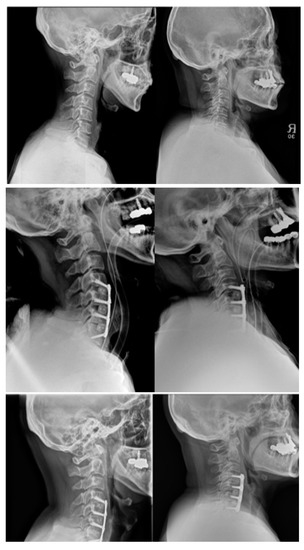

2.2. Evaluation of Radiologic Outcomes

- C2–7 Cervical Lordosis (CL): Cobb’s Method. This was measured by the angle formed by the perpendicular lines parallel to the inferior endplates of C2 and C7 [12].

- C2–7 Sagittal Vertical Axis (SVA): the distance between the C2 plumb line and the posterosuperior corner of C7 [12].

- Plate-to-Disc Distance: distance from the most proximal part and most distal part of the plate to the superior and inferior adjacent disc spaces, respectively [13].

- Screw Angles: angle between a line perpendicular to the plate and the direction of the screw [6].

- Subsidence: the vertical length from the superior endplate of the most superior vertebra to the inferior endplate of the most inferior vertebra [14].